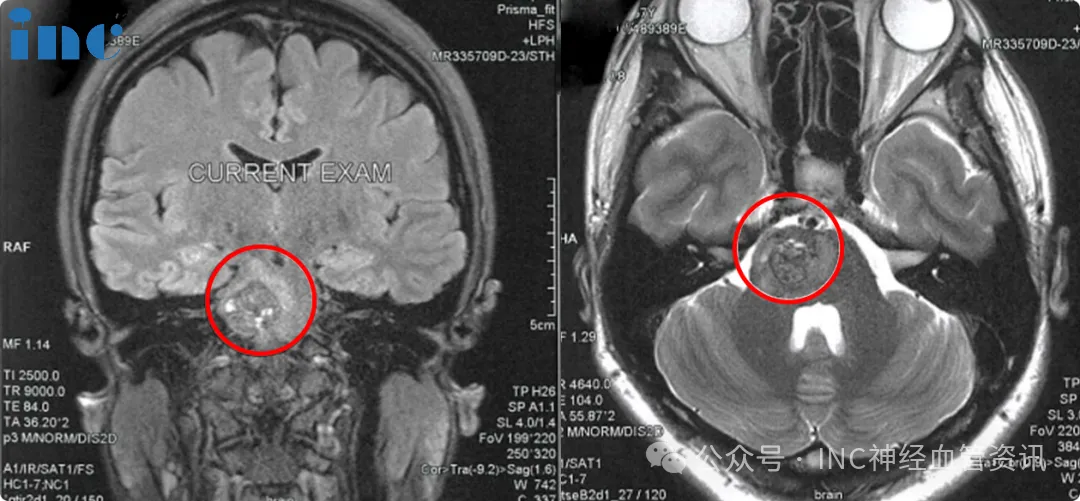

时光流转,术后两年,佩珊的最新复查核磁共振结果正式出炉,影像清晰显示:脑干桥脑海绵状血管瘤已完全切除,无任何残留,病灶无复发迹象。那行"COMPLETE cavernoma removal(病灶全切)"的报告结论,终于为这段漫长的抗病历程画上了圆满的句号。